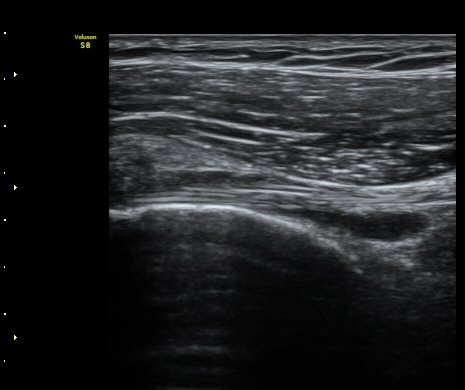

¼ºº° / ³ªÀÌ

¿©ÀÚ/ 50¼¼

ÁÖÁõ»ó

³Ñ¾îÁø ÈÄ ½ÉÇØÁö´Â ¾î±úÀÇ ÅëÁõ°ú °­Á÷

º´·Â

³Ñ¾îÁø ÈÄ ¾î±úÀÇ ÅëÁõÀÌ ¹ß»ýÇÏ¿© Ÿ º´¿ø ³»¿øÇÏ¿© ¿¢½º·¹ÀÌ °Ë»ç¿¡¼­ ƯÀÌ ¼Ò°ß ¾ø´Ù´Â ¼Ò°ßÀ» µè°í Áö³ÁÀ¸³ª ¾î±úÀÇ ÅëÁõÀÌ ½ÉÇØÁö°í Á¡Á¡ ¾î±ú°¡ ±»¾îÁ® ³»¿ø

ÃÊÀ½ÆÄ °Ë»ç